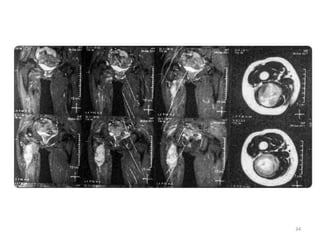

• Then after 3 months, the patients entered in

deep coma after liver metastases then died.